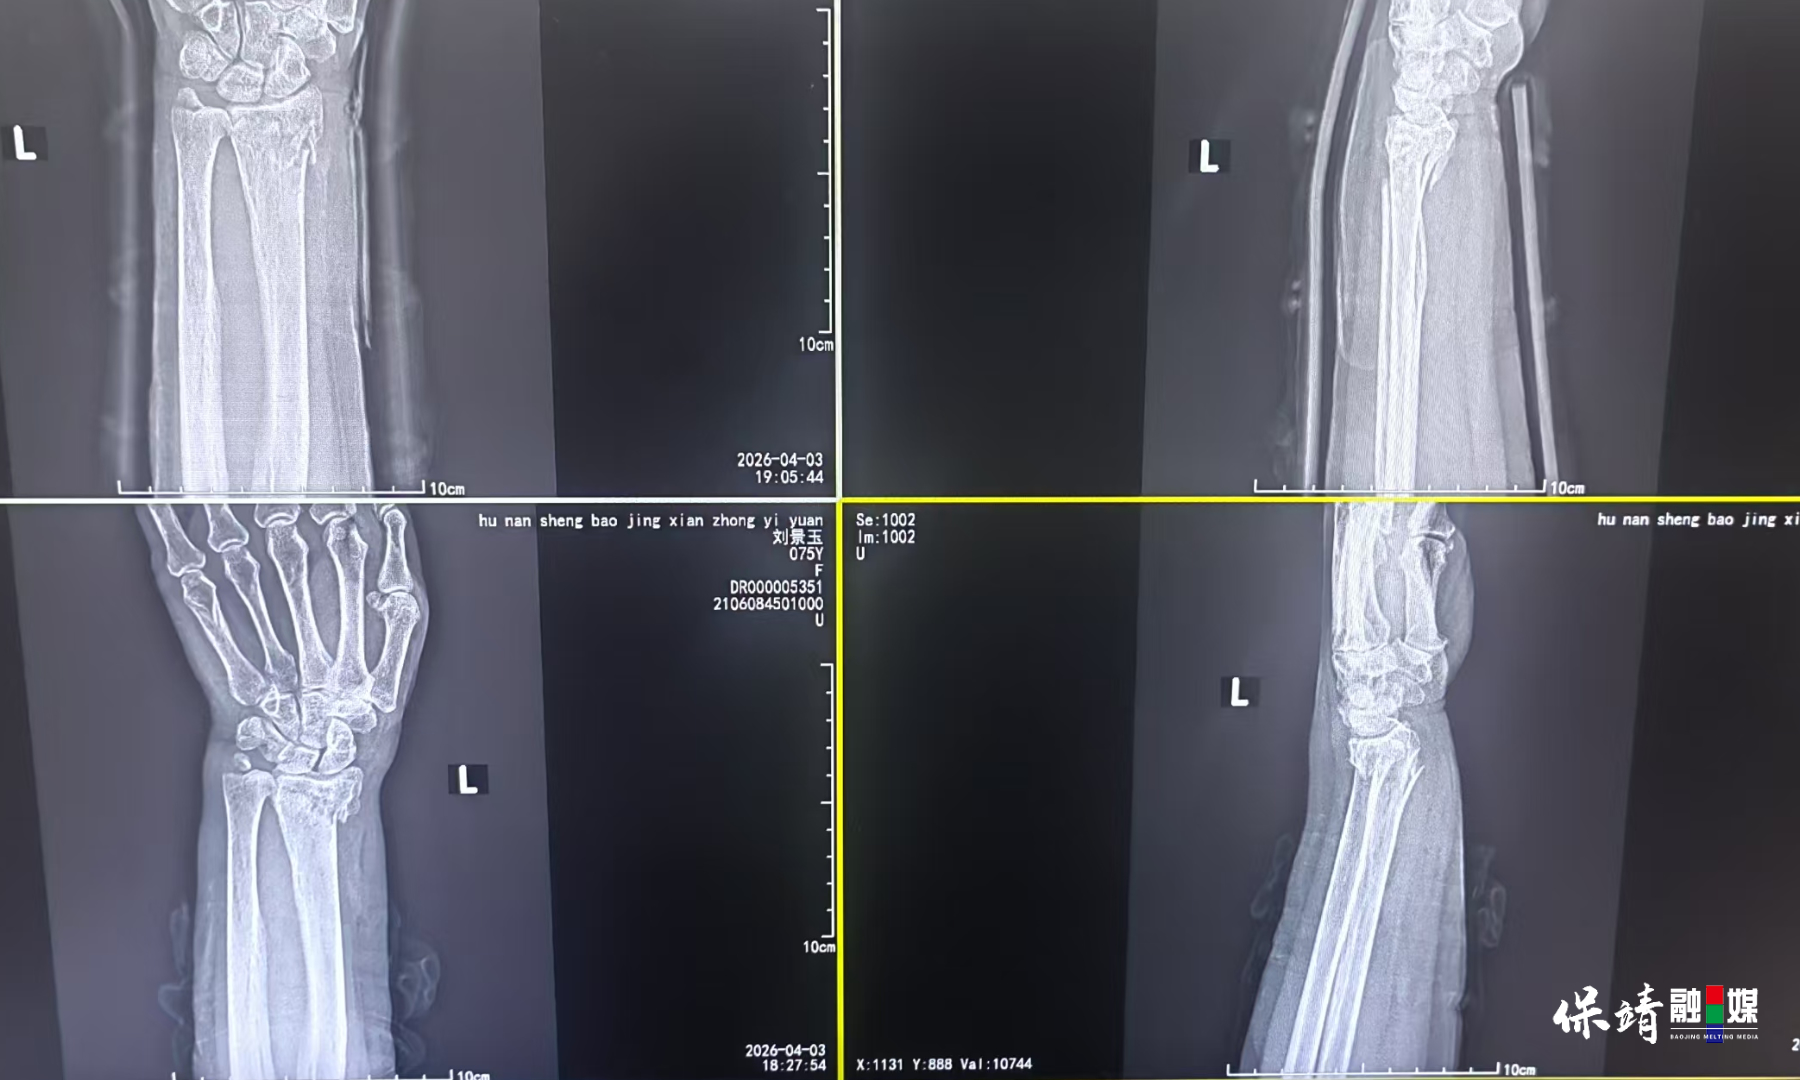

保靖县融媒体中心4月5日讯(通讯员 蔡春燕 彭书凤)“医生正的是骨,用的是手,安的是我的心。”4月3日,74岁的刘女士不慎摔倒致左手受伤,在保靖县中医院接受中医手法正骨后,感慨地说道。

当天,刘女士被家人送到保靖县中医院。骨伤二科主任梁先海接诊后,诊断为柯雷氏骨折(桡骨远端距关节面2-3厘米骨折)。考虑到刘女士希望保守治疗,梁先海在仔细体查和阅片后,为她制定了局麻下中医手法正骨的个性化方案:先理筋,再采用“一拉二抖三屈掌四尺偏”的中医正骨手法复位,随后外用中药涂擦、自制硬膏外敷,并用自制小夹板固定,最后检查血运和手指活动。“一根自制小夹板、几双巧手,不用开刀,无需钢钉,就能将错位的骨骼复位如初。”刘女士说。

在保靖县中医院骨二科,这样的场景并不鲜见。梁先海介绍,对于桡骨远端骨折、前臂尺桡骨双骨折等骨科疾病,中医通过正骨、小夹板固定等非手术方法,常能达到与西医手术相当的疗效,且费用更低。自2025年保靖县师承湘潭市中医院正骨科主任曹谦教授以来,医院专门设立了中医正骨科。2025年全年接诊的100多例此类骨折患者,均通过中医正骨实现复位,基本未再实施切开复位内固定手术。